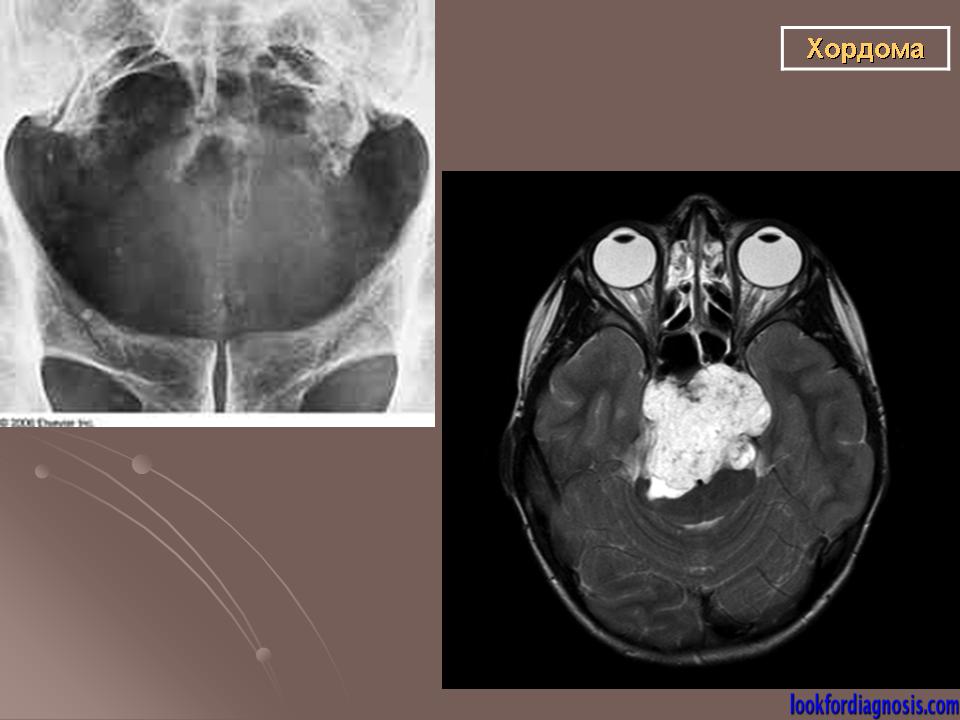

Хордомы могут достигать больших размеров, особенно при их локализации в каудальном отделе позвоночника. Клиническая картина во многом зависит от направления роста хордомы. При росте в спинномозговой канал опухоль вызывает симптомы сдавления спинного мозга, конского хвоста и корешков нервов.

Для хордом различных локализаций, выявлены наиболее характерные симптомы. Так, селлярные хордомы чаще проявляются глазодвигательными нарушениями (III нерв - 43%, VI нерв - 59%), и у трети больных эндокринными нарушениями (чаще гипотиреоз, гипокортицизм, гипогонадизм). У больных с хордомами ската типичными симптомами были поражение отводящего (79%), тройничного нерва (65%) и туловищная атаксия (55%). Симптомы поражения VII, VIII, IX или X черепных нервов были у трети больных с этой локализацией опухоли. Клиника при локализации хордом в краниовертебральной области представлена, как правило, характерным симптомокомплексом. Поражаются черепные нервы с VI по XII (VI -53%, VII - 33%, VIII - 27%, IX и X - 77%, XI - 48%, XII - 62%), у части больных имеют место тетрапарез или гемипарез. Нередко обращает на себя внимание вынужденное положение головы или ограничение объёма движений (поворотов и наклонов головы), боль и "хруст" в шее.